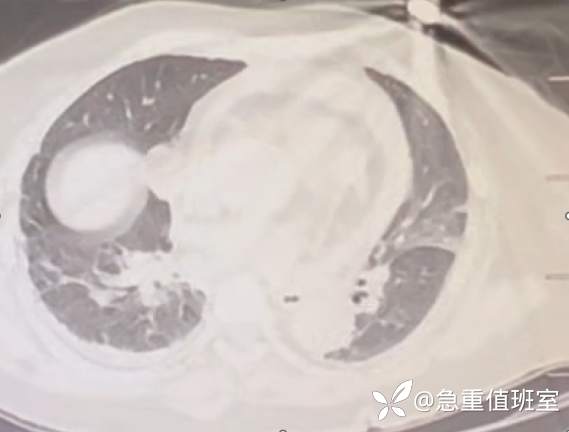

- 主动脉 CTA:急性主动脉夹层 A 型。

图 3 主动脉 CTA